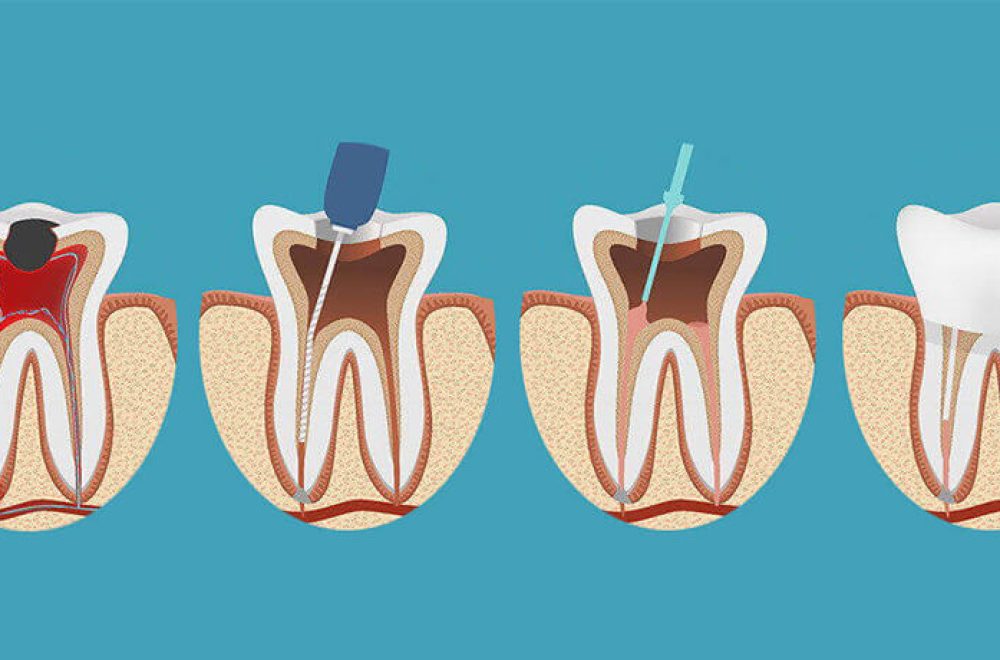

Uzman diş hekimi ya da endodontist tarafından yapılabilen kanal tedavisinde ilk adım röntgen çekimidir. Röntgen aracılığıyla diş kökünün içindeki kanalların durumu ve çevre dokularda enfeksiyon olup olmadığı görüntülenir. Buna göre uzman hekim tarafından dişe uygulanacak kanal tedavisi planlanır.

İkinci aşamada anestezi devreye girer. Kanal tedavisi lokal anestezi eşliğinde gerçekleştirilen bir tedavi yöntemidir. Anestezi aracılığıyla dişin yanındaki bölge uyuşturulur.

Üçüncü adımda diş içine bir kavite (delik) açılır. Söz konusu boşluktan girilerek sorunlu pulpa bölgesi, çürümüş haldeki sinir dokusu ve enfeksiyonlu partiküller çıkarılır. Dişin içi tamamen temizlenerek dezenfekte edilir.

Dördüncü aşamada doldurma işlemi gerçekleştirilir. Pulpayı ve diş sinirini çıkarmak amacıyla diş kökünde açılan boşluk özel bir kauçuk bileşeni kullanılarak doldurulur. İnsan vücuduyla uyumlu, herhangi bir alerjik reaksiyona yol açmayan guta perka isimli bu maddeyle doldurulan boşluk sayesinde olası enfeksiyonların önüne geçilmesi amaçlanır. Bu aşamanın sonunda kanal tedavisi de tamamlanmış olur.